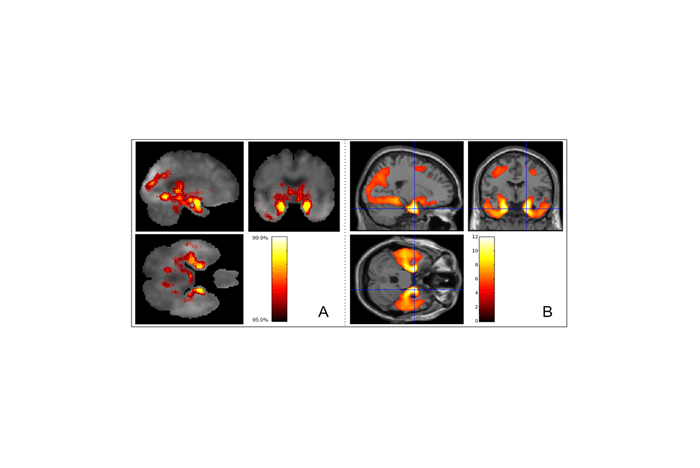

AlphaFold showed us that AI could find patterns in biological data that traditional methods missed. We applied this lesson to Alzheimer's research. Inspired by this multi-modal strategy, we applied similar deep learning techniques across three biological data types: imaging, genomic, and metabolomic data to detect Alzheimer's pathology in its earliest stages.

First, we enhanced brain imaging analysis through pattern recognition. We trained our AI to learn tau accumulation patterns from people who eventually developed dementia, then used this knowledge to identify similar patterns in those still cognitively healthy. Using CNNs with explainable AI techniques, we could spot these high-risk patterns years before symptoms appear.

Second, we used genomics for earlier detection. Since genetic data is fixed at birth, it offers the earliest possible risk assessment. We developed DeepBlock, employing transformer-based architectures similar to those in modern language models, to decode AD-relevant patterns from whole genome sequences.

Third, we used metabolomics for its comprehensive biological information. Unlike static genetic data or expensive imaging, metabolomic profiles capture dynamic changes in brain metabolism as the disease progresses. Our c-SWAT analyzes these complex metabolic networks to detect early Alzheimer's signatures.

Our integrated approach creates a comprehensive picture for each patient. By combining tau patterns, genetic markers and metabolic signatures, we can understand where someone stands on the disease spectrum. This allows physicians to have informed conversations with patients about their specific risks and options. A 60-year-old with concerning metabolic changes might benefit from different interventions than someone with genetic risk but no current biological markers.